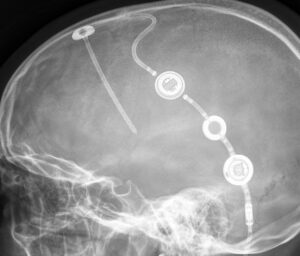

Röntgenbild des M.Scio als inline Variante ohne Reservoir (flat inline) in Kombination mit einem proGAV2.0 Shuntsystem.